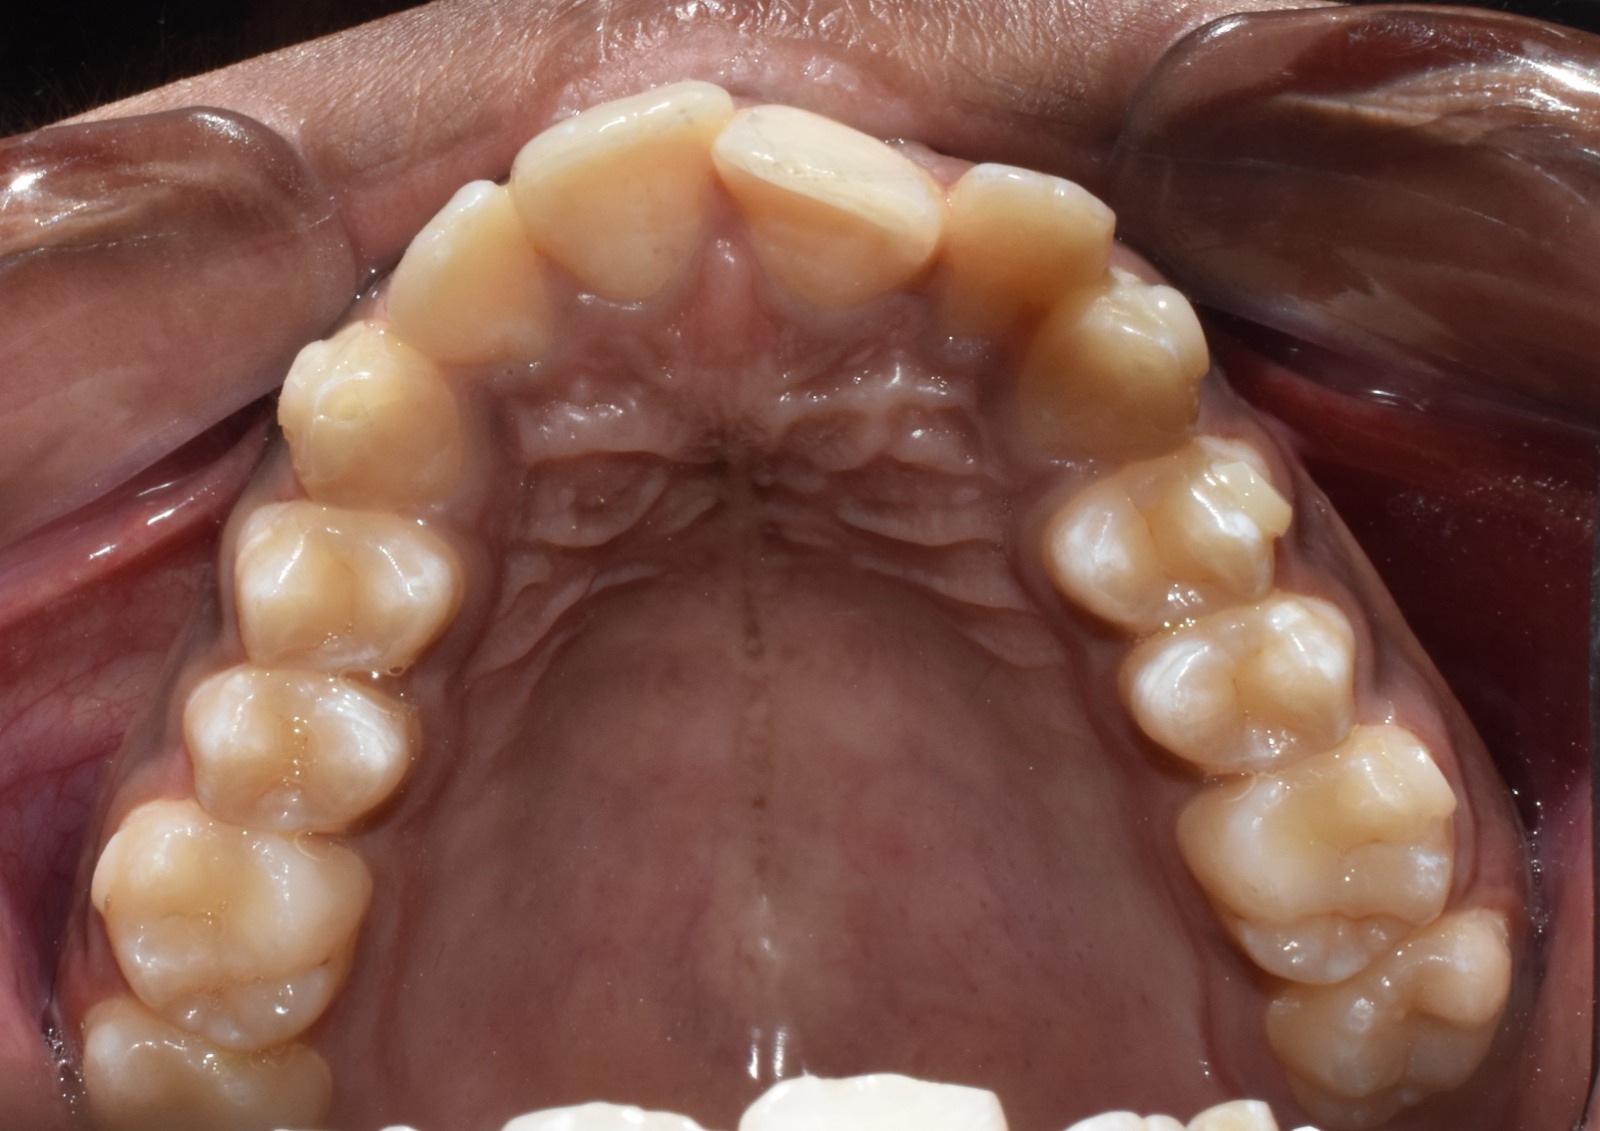

Before & After Results

At Aline Dent, we take pride in delivering visible and lasting improvements in our patients’ smiles. Our before-and-after results highlight the effectiveness of modern dental treatments combined with personalized care. This gallery showcases real dental cases treated at our clinic, giving you a clear idea of how different dental concerns can be corrected with the right treatment approach.

From minor corrections to complete smile enhancements, these teeth transformation results demonstrate how professional dental care can improve both oral health and appearance. Our experienced dental team carefully evaluates each patient’s needs and creates customized treatment plans to achieve natural, healthy, and confident smiles.

In this gallery, you will find a variety of smile makeover cases, including treatments for crooked teeth, gaps, discoloration, damaged teeth, and other common dental concerns.